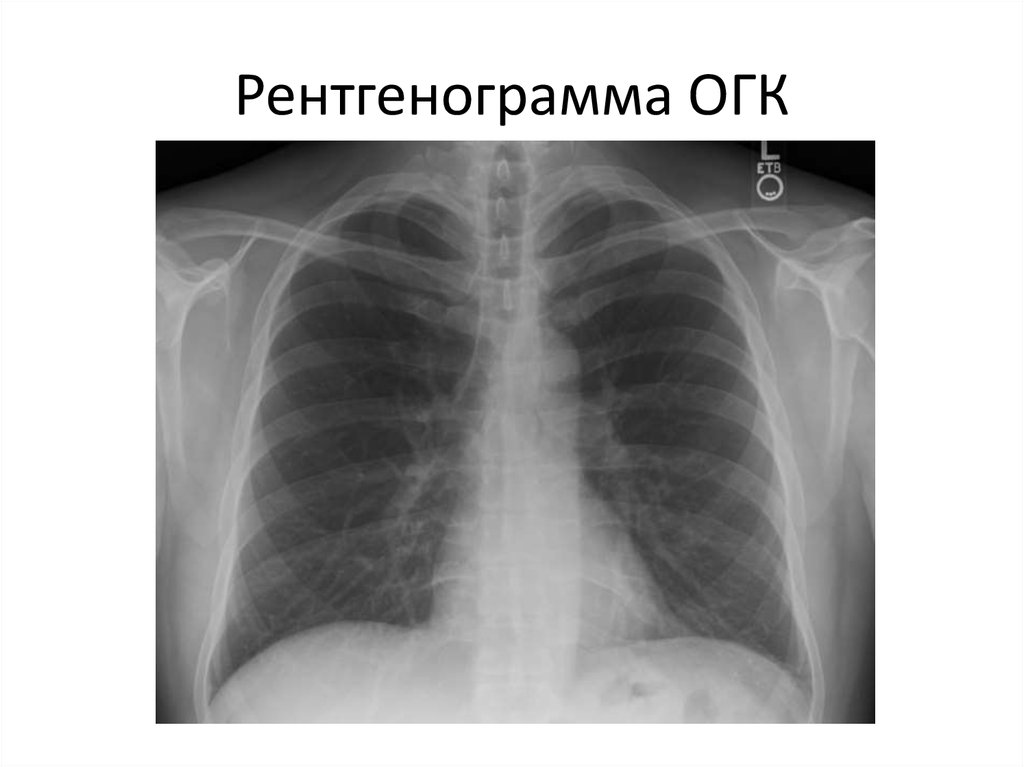

34. Рентгенограмма ОГК